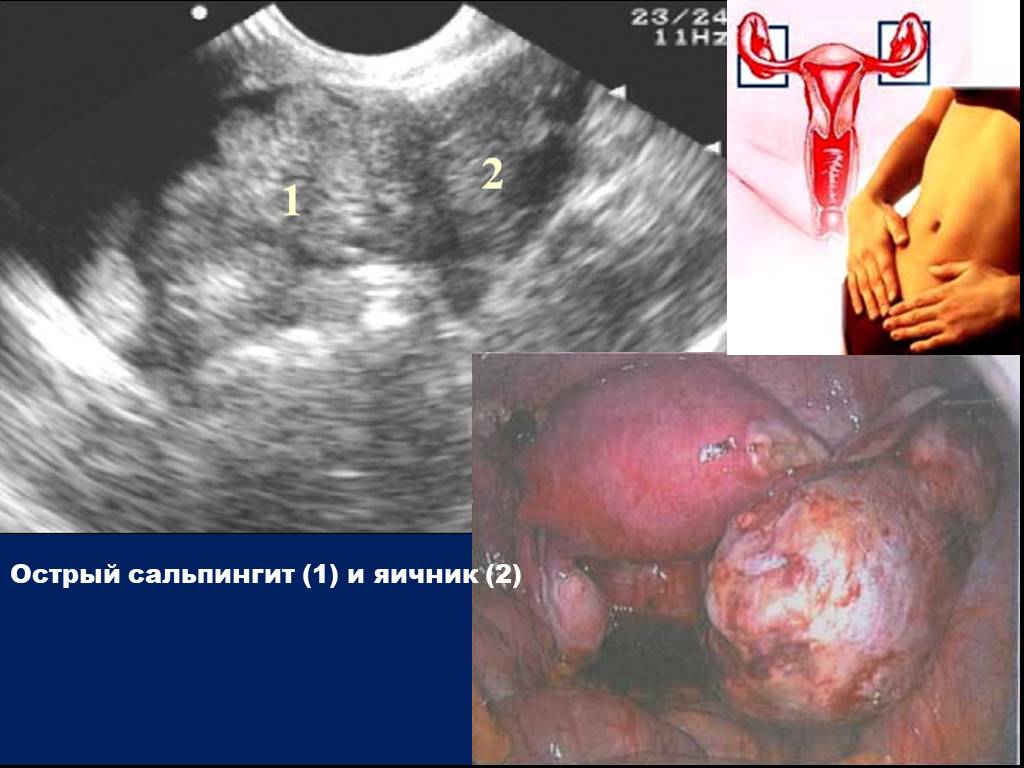

Диагностика болезни

Симптомы недуга схожи с внематочной беременностью, аппендицитом, кистой яичника. Чтобы поставить правильный диагноз, должны проводят обследования. Методы диагностики:

Своевременное использование вышеперечисленных методов обследования позволяет вовремя приступить к лечению, получить шанс на полное выздоровление, восстановление репродуктивной функции женщины.